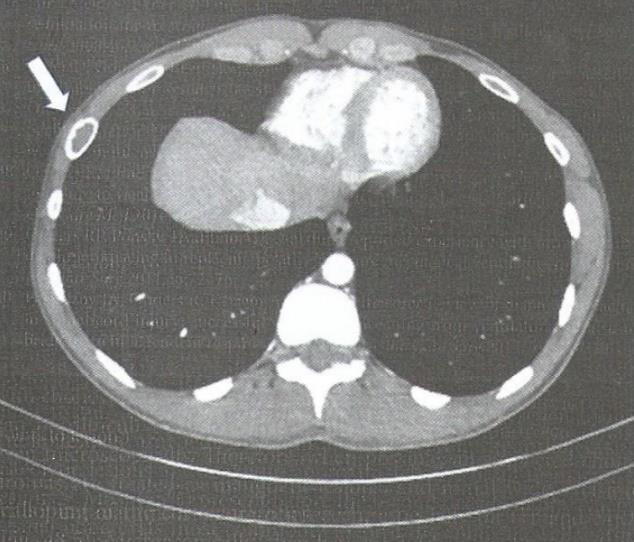

Paciente de 28 anos, apresenta achado tomográfico em arco costal revelado pela seta na figura a seguir.

Fonte: Locicero e col. (2019).

O provável diagnóstico é: